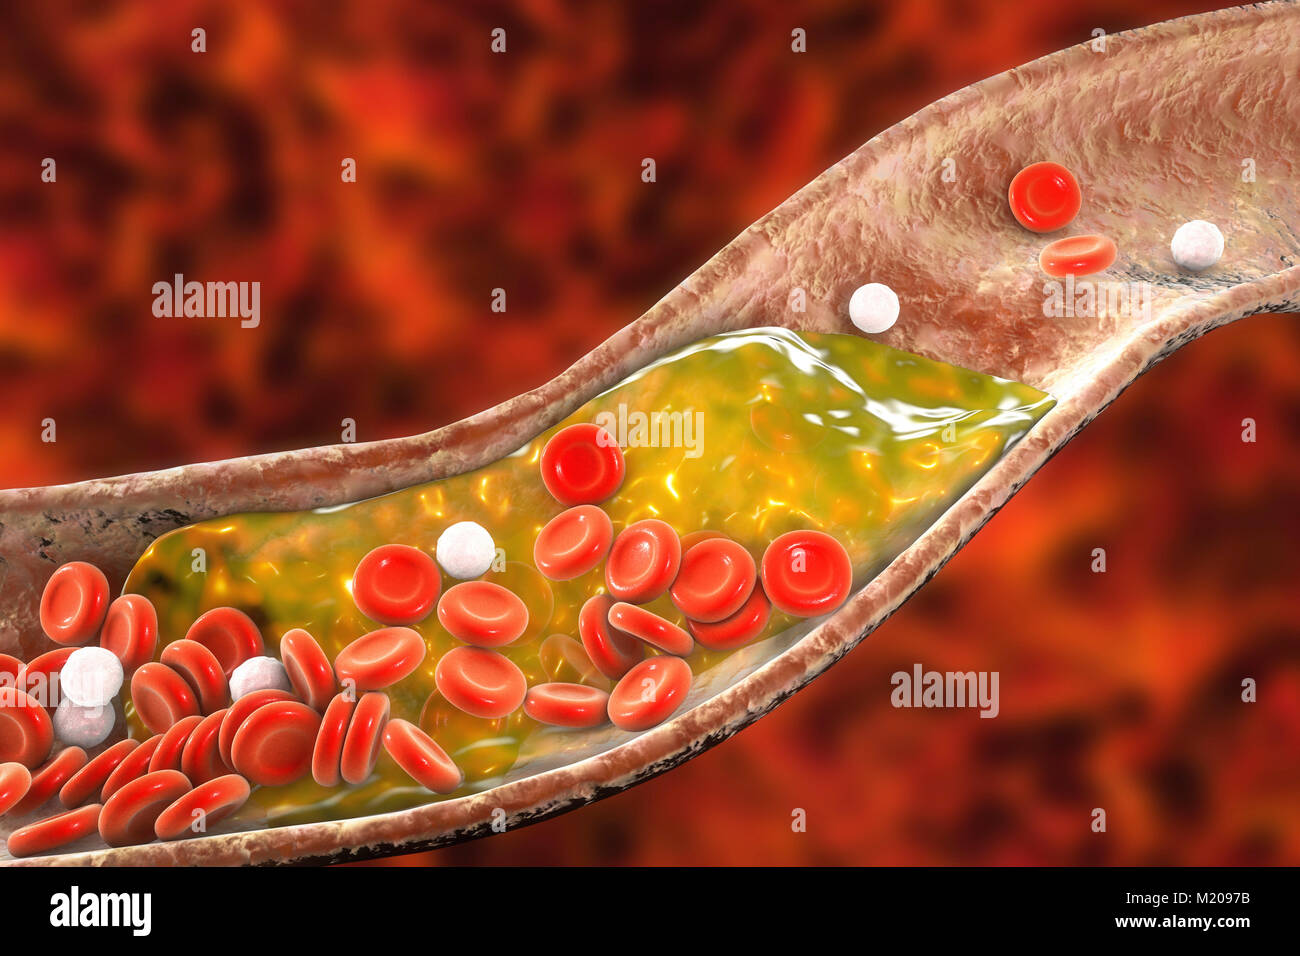

Atheromatous plaque inside blood vessel, computer illustration. A cholesterol atheroma is causing a narrowing of an artery (atherosclerosis). Stock Photohttps://www.alamy.com/image-license-details/?v=1https://www.alamy.com/stock-photo-atheromatous-plaque-inside-blood-vessel-computer-illustration-a-cholesterol-173340259.html

Atheromatous plaque inside blood vessel, computer illustration. A cholesterol atheroma is causing a narrowing of an artery (atherosclerosis). Stock Photohttps://www.alamy.com/image-license-details/?v=1https://www.alamy.com/stock-photo-atheromatous-plaque-inside-blood-vessel-computer-illustration-a-cholesterol-173340259.htmlRFM2097F–Atheromatous plaque inside blood vessel, computer illustration. A cholesterol atheroma is causing a narrowing of an artery (atherosclerosis).